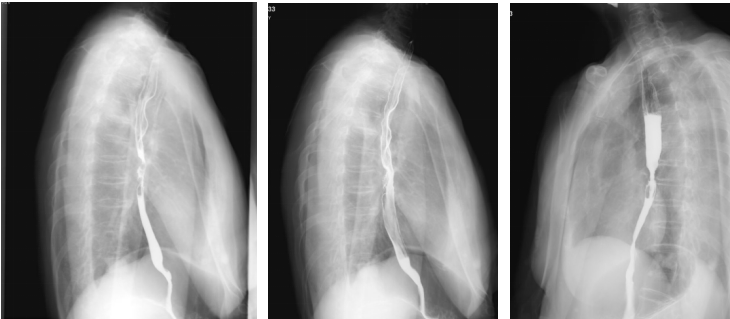

上消化道钡剂造影(2020-08-14):相当于胸7-9椎体水平的食道见范围长约35mm的狭窄段,管壁僵硬,粘膜皱襞破坏、中断,轮廓不光整,可见偏心性充盈缺损及小刺状龛影,狭窄段以上食管轻度扩张,对比剂排空延迟,余食道壁柔软,粘膜规则,未见充盈缺损及龛影,未见异常狭窄及扩张,贲门结构正常,开闭自如。

2020-08-27行放疗CT定位。2020-09-07~2022-10-23行肺部、食管放疗。

GTVp1为食管肿瘤,GTVp2为肺肿瘤。

分割方式:

95%PGTVp1:60Gy/2Gy/30F;

95%PGTVp2:60Gy/2Gy/30F;

后肺原发灶补量照射:95%PGTVp2:8Gy/2Gy/4F。

放疗同期行同步化疗+靶向治疗,具体方案为:洛铂50mg d1 q21d+尼妥珠单抗400mg Qw。放化疗前开始行重组人血管内皮抑制素(恩度)30mg d1-7q3w抗血管靶向治疗。放化疗结束后给予抗血管靶向及针对肺原发灶TKI靶向治疗维持,TKI靶向:克唑替尼250mg Bid po Qd。治疗后3个月,患者拒绝继续恩度靶向治疗。治疗后6月患者拒绝克唑替尼治疗。考虑肺癌为驱动基因阳性型,未能行食管癌治疗后免疫治疗维持。